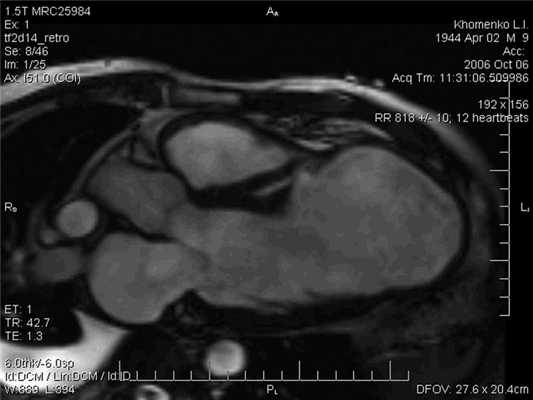

Топическая диагностика разрыва МЖП не представляла больших трудностей; у всех больных при эхокардиографии (ЭхоКГ) в допплеровском режиме регистрировали лево-правый сброс крови через дефект МЖП. Помимо стандартных методов диагностики постинфарктных разрывов МЖП, включающих физикальное обследование, электрокардиографию, рентгенографию и ЭхоКГ, в данном исследовании довольно широко использовались возможности магнитно-резонансной томографии (МРТ). Этот метод позволяет с высокой точностью определить локализацию, размер и характер разрыва (рис. 1 и далее на цв. вклейке). Рисунок 1. Магнитно-резонансная томография сердца с разрывом межжелудочковой перегородки в стадии рубцевания инфаркта миокарда (указан стрелкой). Кроме того, данное исследование дает возможность оценить линейные и объемные размеры сердца, протяженность рубцовых изменений, жизнеспособность и сократимость миокарда вне зоны инфаркта. Недостатком МРТ является невозможность ее выполнения у тяжелых, нетранспортабельных больных, находящихся на искусственной вентиляции легких, и у больных с имплантированным электрокардиостимулятором.

По обобщенным результатам ЭхоКГ и МРТ локализация разрыва МЖП у всех больных совпадала с локализацией ИМ, средний диаметр дефекта составлял 19,4±7,8 мм.